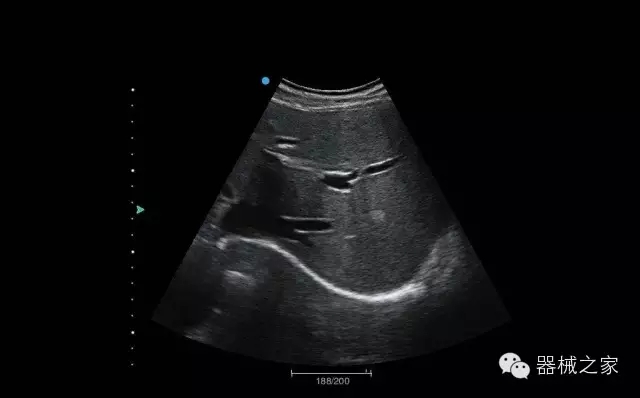

品牌:理邦儀器(EDAN)

經(jīng)典產(chǎn)品:Acclarix AX8

臨床圖片賞析

臍帶血流